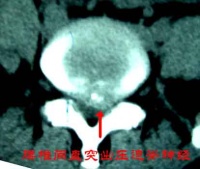

典型腰椎间盘突出CT[编辑 | 编辑源代码]

L4-5间盘层面可见后突丘状软组织影,前后径5mm ,居中偏右,CT值78hu,椎管前后径8mm,硬膜囊明显受压,L5-6间盘层面可见后突丘状软组织影,前后径4mm ,居中偏右,CT值71hu,余所扫各椎间盘层面均未见明显膨突征象。

3D: 生理曲度存在,椎体;附件未见异常,间隙无狭窄。

印象: L4-5;5-S1 椎间盘突出症,以L4-5为著伴继发椎管狭窄。